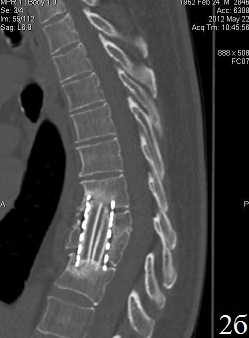

Рис. 2. Пациент У. Титановая блок-решетка с аутокостью через 6 месяцев (А) и через 12 месяцев (Б.) после операции. Отсутствие зоны резорбции вокруг имплантата без выраженного склероза, полная ассимиляция трансплантата с ложем

Через 12 месяцев после операции (табл. 4) в группе 1, несмотря на более выраженную резорбцию (6,43±1,06 мм), сагиттальный профиль позвоночника стабилизируется в сравнении с предыдущим периодом, при этом частичная стабилизация позвоночника появляется на фоне выраженного склероза за счет массивных краевых костных разрастаний. В то же время, в группе 2 у всех больных стабильность передней колонны обеспечивается полной ассимиляцией трансплантатов с ложем позвонков.

Титановые меши, непосредственно не врастая в костную ткань, обеспечивают опорную функцию и стабильность реконструируемого отдела позвоночника, создают благоприятные условия для срастания костных трансплантатов с реципиентным ложем в достаточно ранние сроки (3-6 мес.) без формирования костных разрастаний и реактивного склероза.